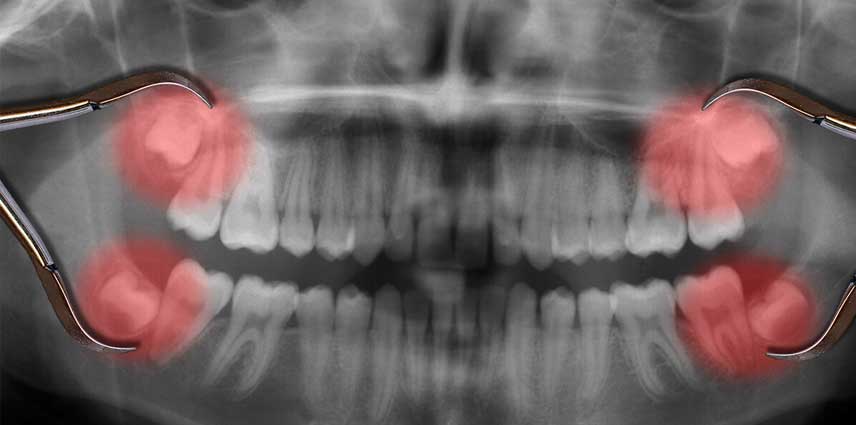

Wisdom tooth extraction

At Accident Clinic, we offer expert wisdom tooth extraction services designed to relieve pain, prevent complications, and support your overall oral health. Whether your wisdom teeth are impacted, infected, or causing crowding, our skilled dental team is equipped to perform both routine and surgical extractions with precision and care.

Using advanced diagnostic tools and modern techniques, we ensure a safe and comfortable experience, even in urgent or emergency cases. Our clinic prioritizes patient comfort, offering local anesthesia and sedation options as needed. After your procedure, we provide clear post-operative instructions and follow-up care to promote quick healing and reduce the risk of infection or other issues.